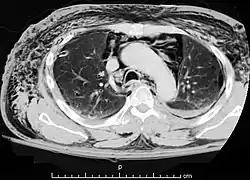

| A CT scan showing air in the mediastinum | |

Pneumomediastinum (from Greek pneuma – "air", also known as mediastinal emphysema)[1] is pneumatosis (abnormal presence of air or other gas) in the mediastinum, the central part of the chest cavity. First described in 1819 by René Laennec,[2][3] the condition can result from physical trauma or other situations that lead to air escaping from the lungs, airways, or bowel into the chest cavity. In underwater divers it is usually the result of pulmonary barotrauma.[1]

Pneumomediastinum is uncommon and occurs when air leaks into the mediastinum. The diagnosis can be confirmed via chest X-ray showing a radiolucent outline around the heart and mediastinum or via CT scanning of the thorax.